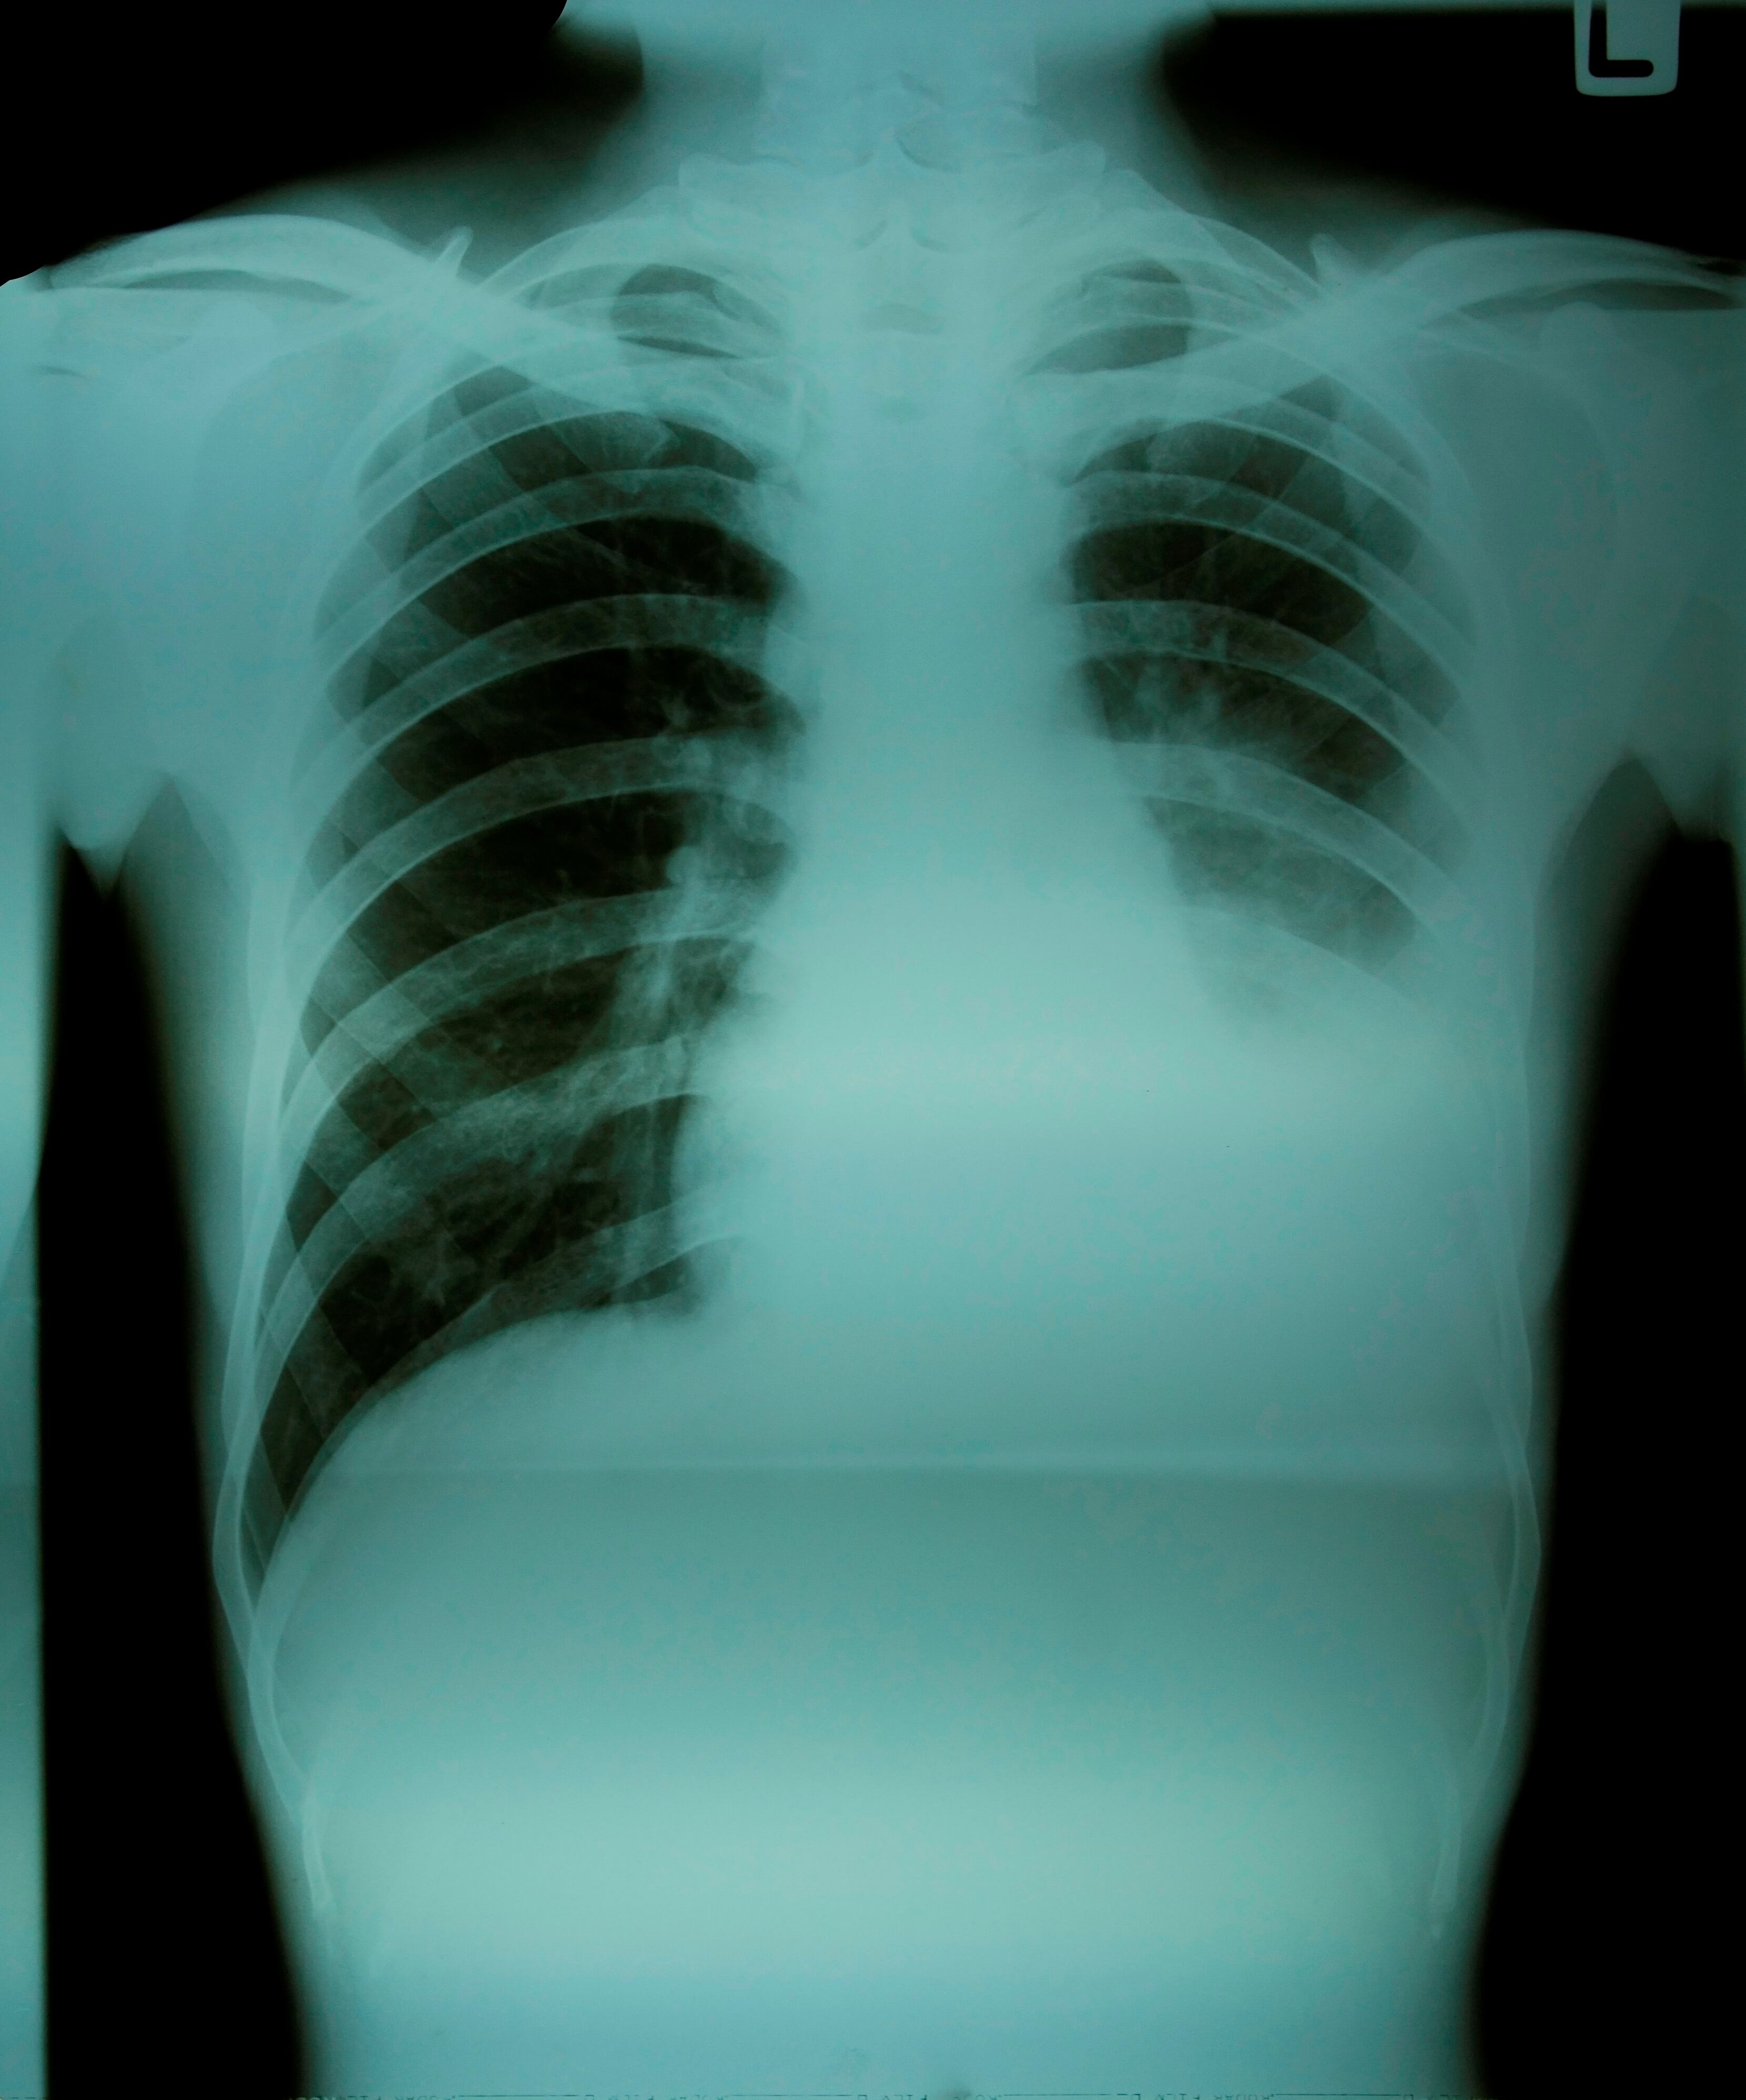

También mantener en aislamiento y con vigilancia médica todos los casos de tuberculosis pulmonar con transmisibilidad potencial, por lo que se deben realizar además adecuaciones locativas y de protección para el personal que labora en el penal.

Esta búsqueda activa de casos al interior de la cárcel La 40 busca no solo evitar la propagación de la tuberculosis pulmonar, sino que los infectados no entren en contacto con pacientes que presenten enfermedades inmunosupresoras.